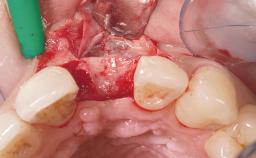

Immediate Flapless Placement of an Implant in a Maxillary Right Lateral Incisor Site

This 43-year-old male patient, a non-smoker, came to our practice because of a fracture of tooth 12 caused by a bicycle accident. Due to the combined para- and infrabony crown and root fracture, tooth extraction, and subsequent implant placement were suggested to the patient as the therapy of choice. The patient had high esthetic expectations with regard to the treatment outcome and asked for an immediate fixed provisional restoration. His individual esthetic risk profile summed up to a medium esthetic risk.

Loading Protocol Immediate

Provisional Implant-Supported Prosthesis Prosthodontic margin > 3 mm apical to mucosal margin Prosthodontic margin > 3 mm apical to mucosal margin